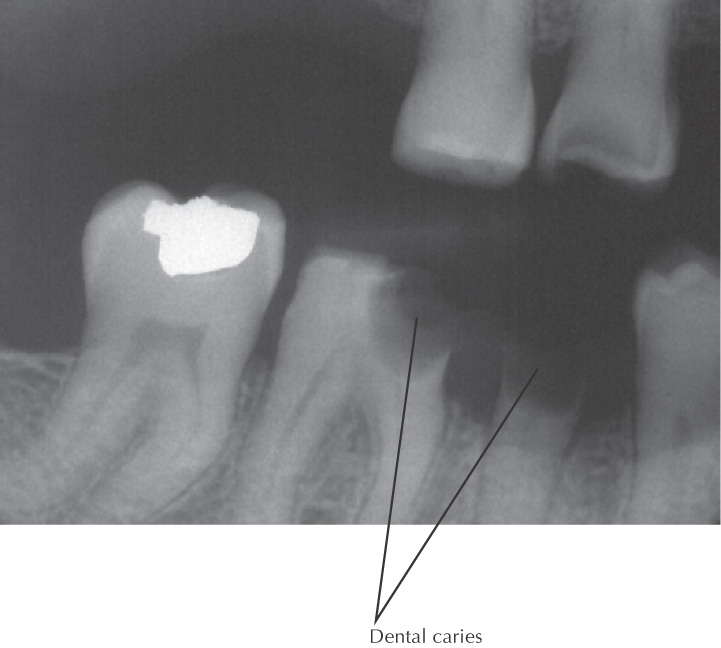

Dental caries (tooth decay), leading to “cavities,” is caused by bacteria in the oral cavity

The bacteria convert foods into acids and help form plaque (made of bacteria, food debris, and saliva), which is deposited on the teeth

Plaque that is not removed from the teeth can mineralize to form tartar

Plaque is most prominent on difficult-to-reach teeth, such as the posterior molars

Acids formed in the plaque begin to erode the enamel on the surface of the tooth, causing a “cavity”

If not treated, the cavity grows in size, with onset of pain as the nerves and blood vessels of the affected teeth become irritated

Consuming foods rich in sugar and starch increases the risk of dental caries

Dental caries can be detected on routine dental examinations

The damage associated with dental caries cannot be repaired by the affected tooth, which now must be restored

Fluoride is used to reduce the risk of dental caries by inhibiting demineralization and promoting remineralization of tooth structure

Saliva helps promote the remineralization process; medications that decrease salivary flow (such as anticholinergics) promote dental caries